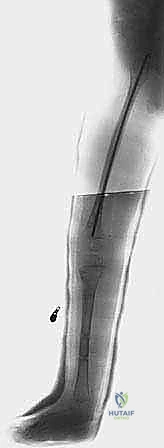

بعد التأكد من استقرار مفصل الورك والركبة، تبدأ مرحلة التطويل. يستخدم الدكتور هطيف أحدث التقنيات العالمية في صنعاء:

* المثبت الخارجي (Ilizarov / TSF): جهاز حلقي يثبت حول الساق، يتم من خلاله إجراء قطع عظمي دقيق (Corticotomy). يقوم الأهل بلف صواميل الجهاز يومياً بمقدار 1 ملم، مما يحفز الجسم على بناء عظم جديد في الفجوة (Distraction Osteogenesis).

| المرحلة الخامسة | 14 - 16 سنة | الجلسة النهائية للتطويل (غالباً باستخدام مسامير داخلية إن أمكن)، إيقاف نمو الطرف السليم جزئياً (Epiphysiodesis) إذا لزم الأمر. | الوصول إلى التساوي التام في طول الطرفين عند البلوغ واكتمال النمو. |